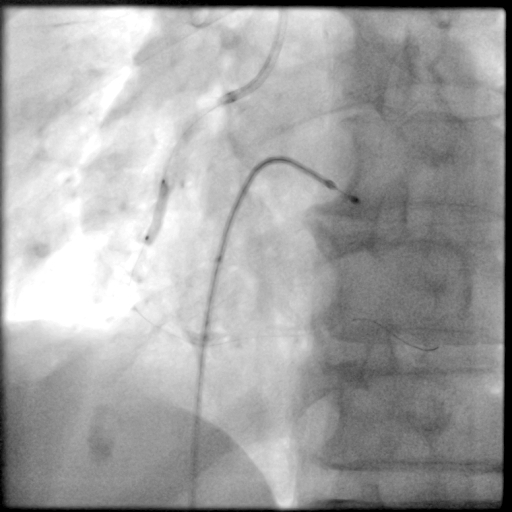

冠脉造影

预置临时起搏器后,7F AL1.0无法到位,更换为7F SAL1.0至RCA开口,应用非顺应性球囊2.5X15mm,于RCA中段病变处以12-18atm扩张,球囊膨胀不佳。